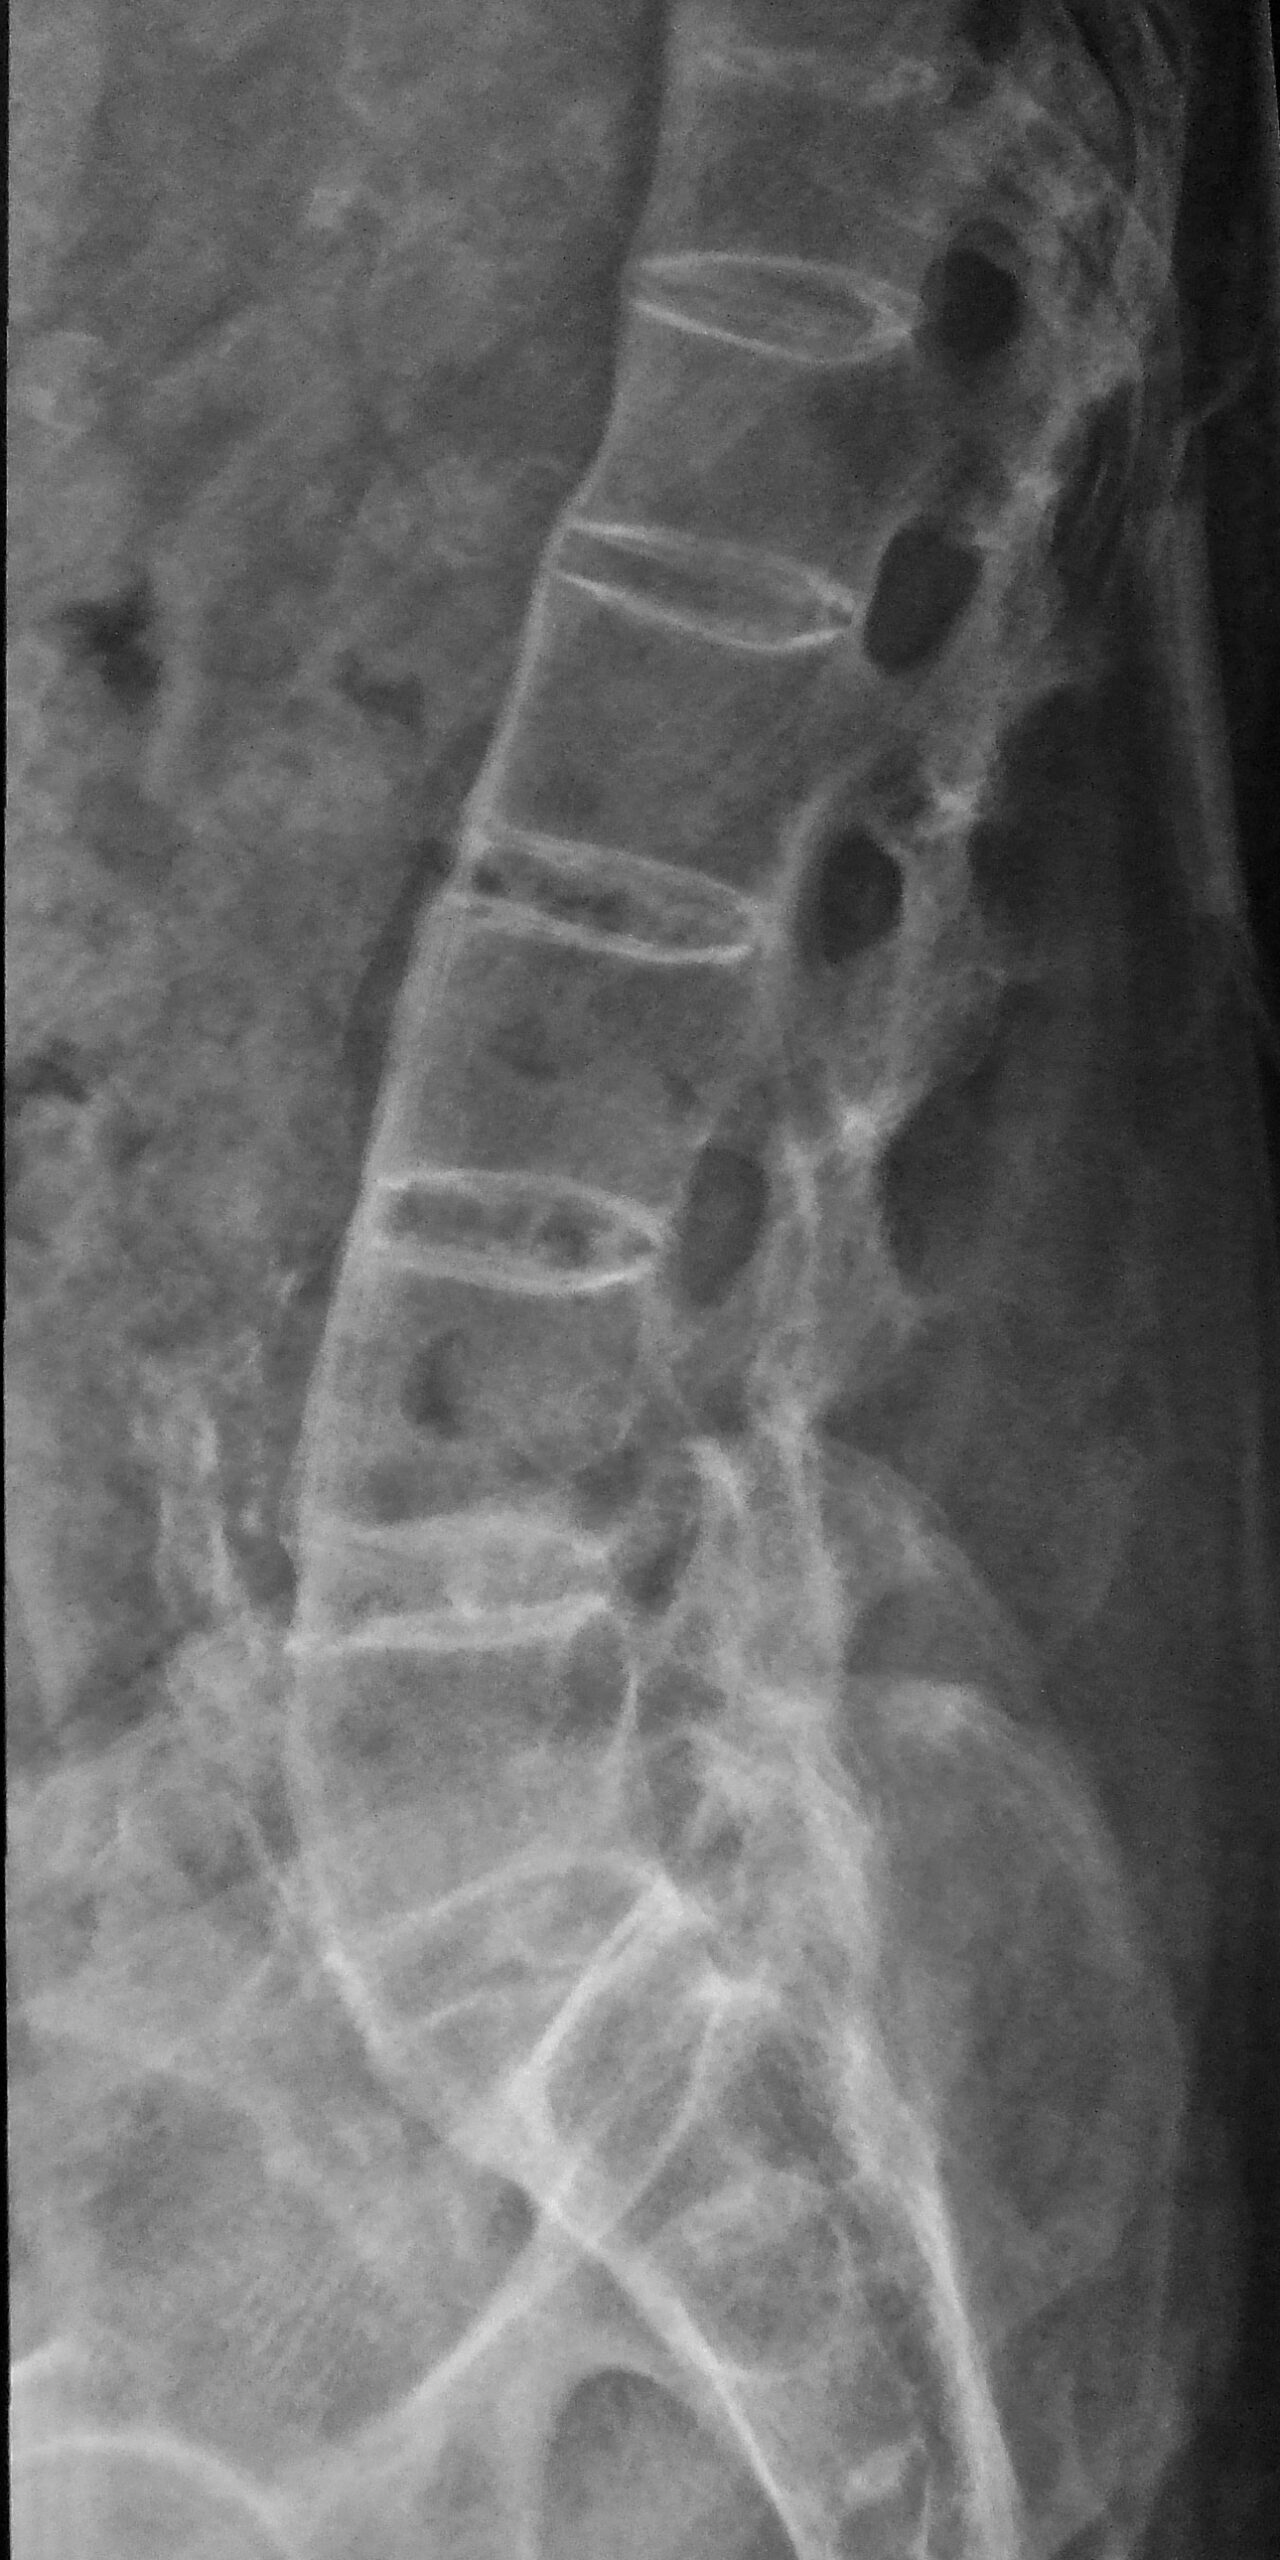

It would be nice to think that the AS somehow “went away” but as you can see from the X-rays below, it has not. Nor did he escape the “fun park of misery” that accompanies many of the arthritides. In Leigh’s case he got the full enchilada; joint fusion, uveitis and urethritis. As bad as that is, and really is bad, Leigh’s life is infinitely better with Chiropractic than it would’ve been without it.

This is Leigh today, 35 years after the initial diagnosis

These are Leigh’s most recent X-rays